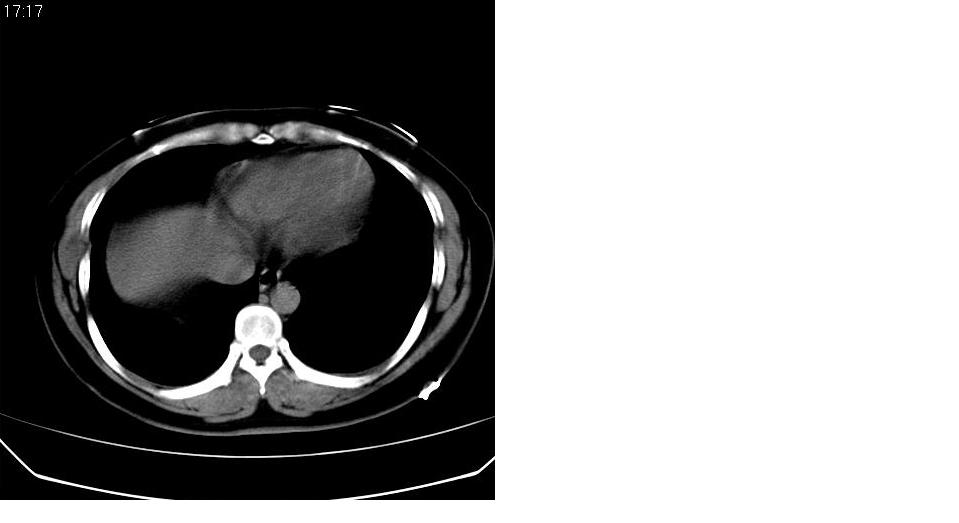

女 40岁,胸片体检发现右肺肿块,无任何症状。

考虑右肺下叶继发肺结核或炎症可能?

下叶背段多发性小腺泡结节,考虑结核。

考虑侵润性结核

考虑右肺下叶背段继发性肺结核。